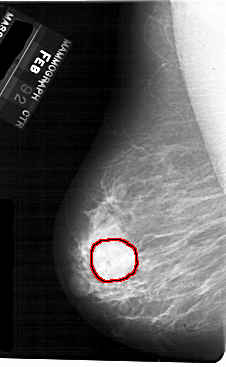

A_1710_1.LEFT_MLO

LEFT_MLO LINES 5491 PIXELS_PER_LINE 3376 BITS_PER_PIXEL 12 RESOLUTION 43.5 OVERLAY

FILE: A_1710_1.LEFT_MLO.OVERLAY

TOTAL_ABNORMALITIES 1

ABNORMALITY 1

LESION_TYPE MASS SHAPE ROUND MARGINS OBSCURED

ASSESSMENT 3

SUBTLETY 5

PATHOLOGY BENIGN

TOTAL_OUTLINES 1

BOUNDARY